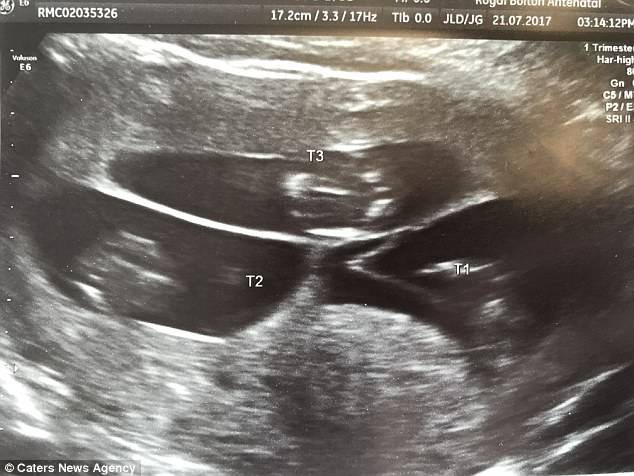

La sonografia ha mostrato che Nicola era incinta non di uno, ma di ben 3 bambini, un tripletta di bimbi non identici.

“Non riuscivamo a crederci. Eravamo spaventati, io però sono riuscita a portare la gravidanza fino a 33 settimane” .